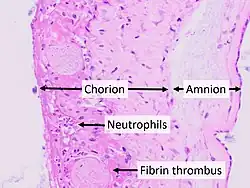

| Micrograph showing acute chorioamnionitis, with neutrophils in the chorion. Also seen are fibrin thrombi, which indicate a severe fetal inflammatory response.[1] H&E stain. | |

Chorioamnionitis is diagnosed from a histologic (tissue) examination of the fetal membranes.[12] Confirmed histologic chorioamnionitis without any clinical symptoms is termed subclinical chorioamnionitis and is more common than symptomatic clinical chorioamnionitis.[2]

Infiltration of the chorionic plate by neutrophils is diagnostic of (mild) chorioamnionitis. More severe chorioamnionitis involves subamniotic tissue and may have fetal membrane necrosis and/or abscess formation.[1]

Severe chorioamnionitis may be accompanied by vasculitis of the umbilical blood vessels due to the fetus' inflammatory cells. If very severe, funisitis, inflammation of the umbilical cord connective tissue, occurs.[12]